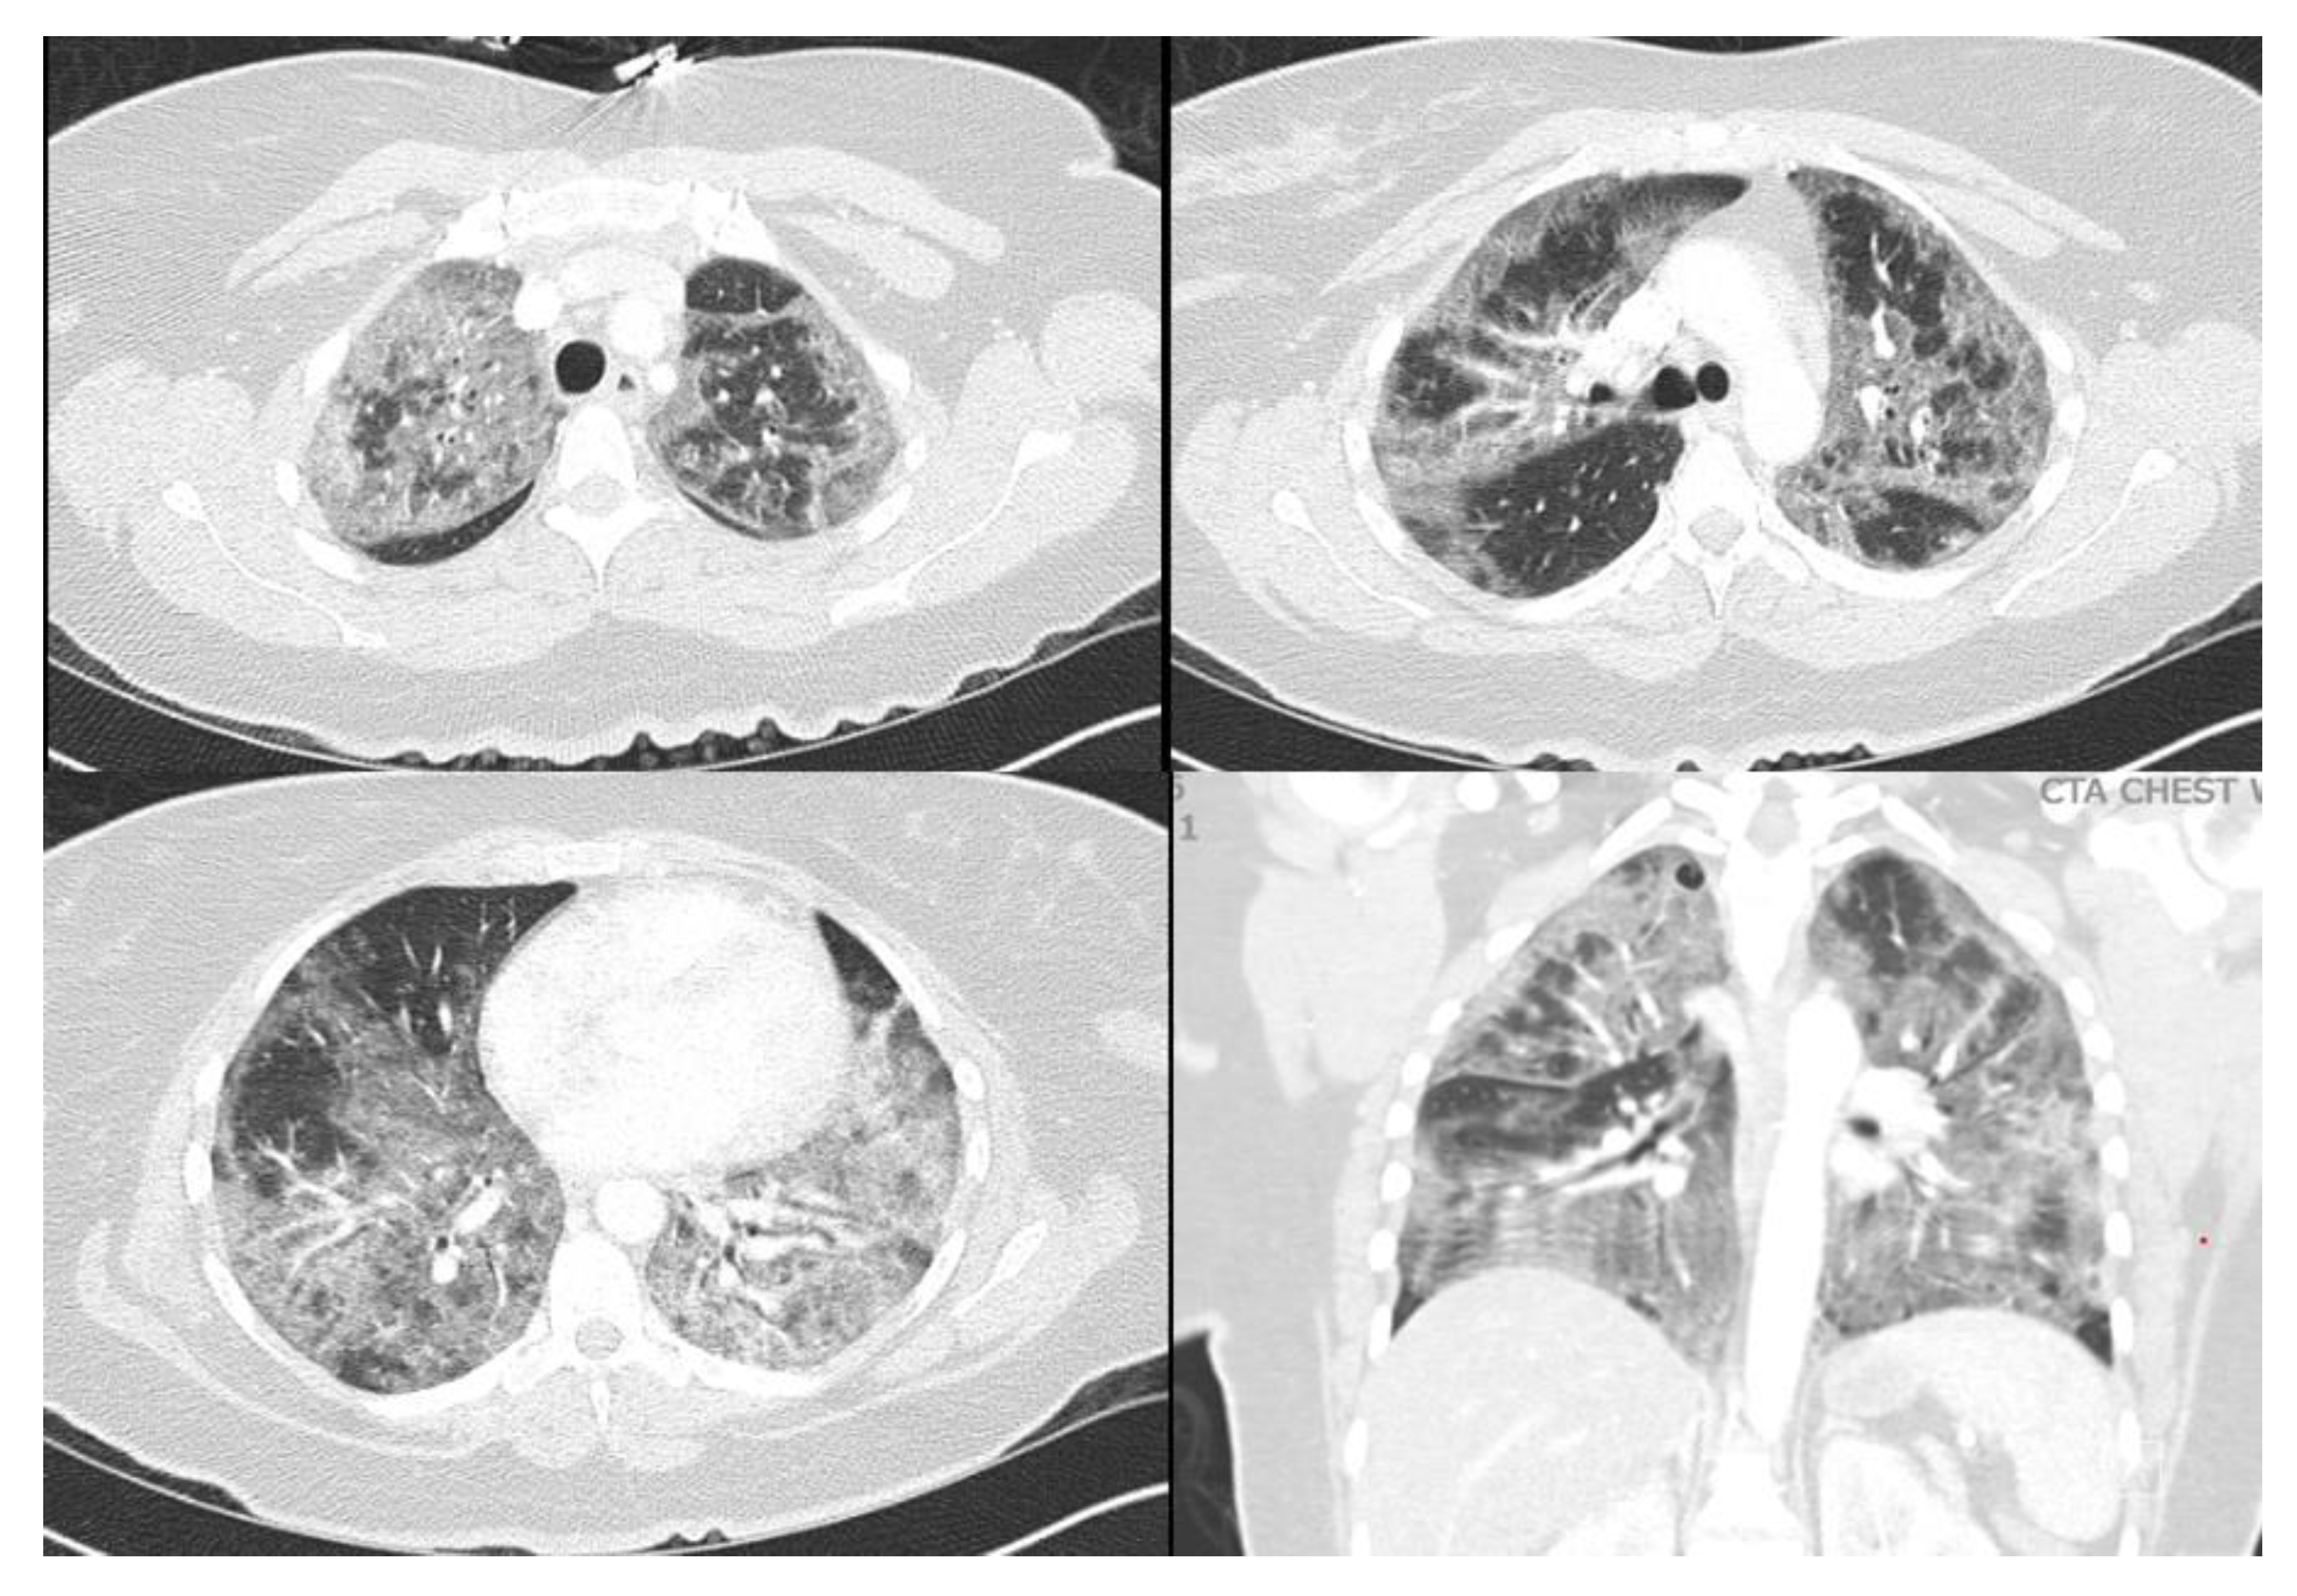

A 40-year-old female with a past medical history of asthma who presented to an outside hospital with a 3-week history of coughing, wheezing, and dyspnea, was found to have extensive bilateral ground glass opacities on CT scan and X-ray of the chest (Figure 1 and Figure 2). Admission testing revealed she was HIV positive with a CD4 count of 9 cells/ml and a viral load of 20,800. Additionally, she tested positive for P. jirovecii via direct immunofluorescence on admission for which she was treated with trimethoprim/sulfamethoxazole (TMP/SMX) and prednisone. Despite ongoing treatment, her clinical status continued to decline necessitating mechanical ventilation 10 days after admission. At this time, she underwent bronchoalveolar lavage which was positive for cytomegalovirus by polymerase chain reaction testing in addition to serum positive CMV (viral load of 175,000), for which ganciclovir was initiated and maintained for 11 days. PCR test of BAL was also positive for CMV, suggesting CMV pneumonia. Unfortunately, she progressed into ARDS refractory to lung-protective ventilation, prone positioning, and inhaled nitric oxide. She was transferred to our facility for evaluation of ECMO therapy at hospital day 18 (8 days after intubation). At the time of transfer, arterial blood gas analysis showed hypoxia (PaO2 of 79 mm Hg) on 100% fraction of inspired oxygen (FiO2), on Bi-level with P high/P low (30/1 cmH2O) and T high/T low (3/0.6 sec). Of note, patient was not able to promptly receive antiretroviral therapy (ART) upon diagnosis of HIV in the setting of ileus due to poor enteral absorption and acute kidney injury. ART with abacavir, lamivudine, and dolutegravir was immediately started on ECMO day 1 when her symptoms of ileus began to resolve.

Figure 1. CT chest on admission demonstrating extensively scattered ground glass infiltrates.